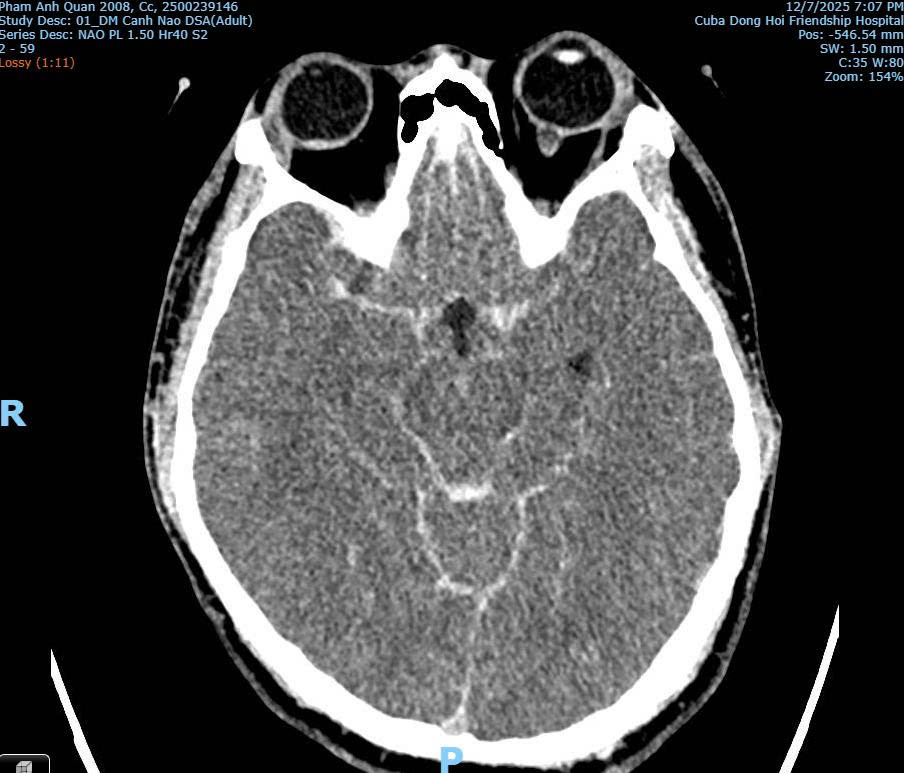

Hình ảnh CT/MRI: Xuất huyết dưới nhện do vỡ phình mạch máu não của bệnh nhân Phạm Anh Q. thời điểm tại Bệnh viện Hữu nghị Việt Nam - Cuba Đồng Hới

Phân tích từ hình ảnh chẩn đoán, bác sĩ Hùng cho biết không phát hiện tổn thương xương cột sống cổ, không có tổn thương vòm sọ, không có tổn thương não do lực tác động bên ngoài. Đồng thời chỉ ghi nhận xuất huyết não lan tỏa và phù não, điển hình của vỡ phình mạch não.

Bác sĩ Hùng khẳng định theo hình ảnh chuyên môn y khoa từ chẩn đoán thì không có dấu hiệu nào cho thấy nạn nhân bị đánh với lực đủ mạnh để gây gãy cổ hoặc chấn thương sọ não do tác động ngoại lực.